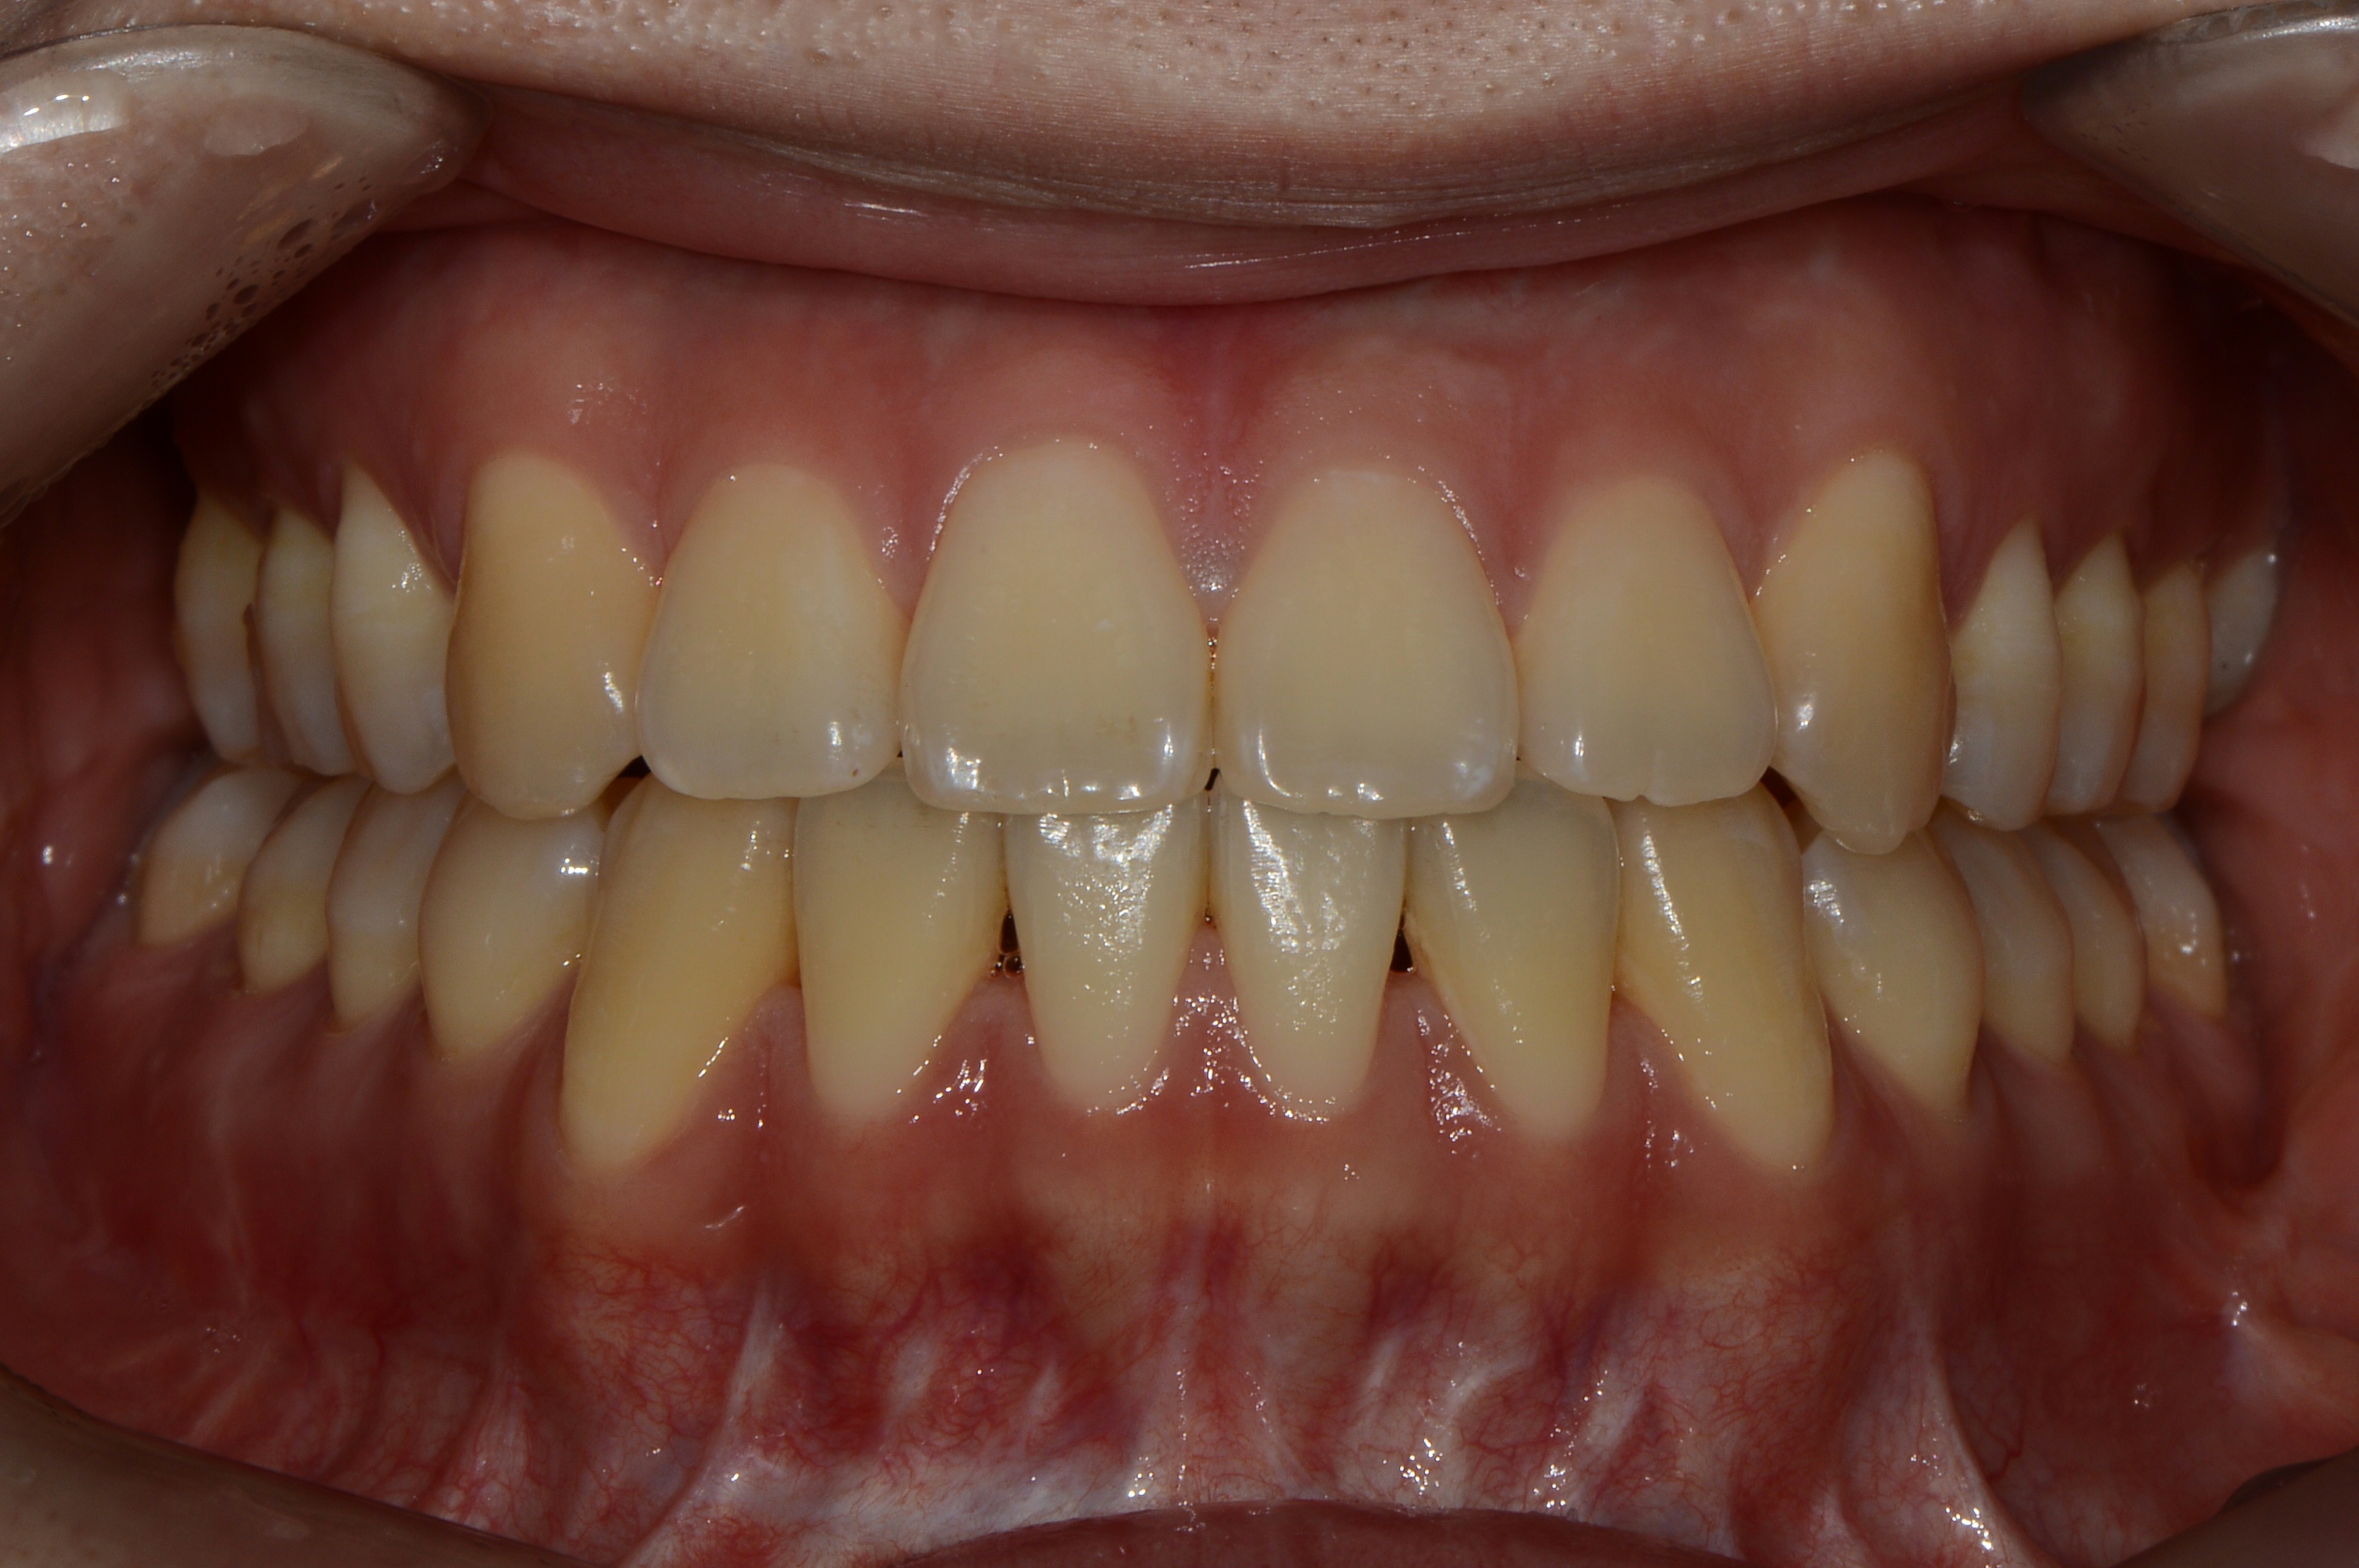

치료 후 사진입니다.